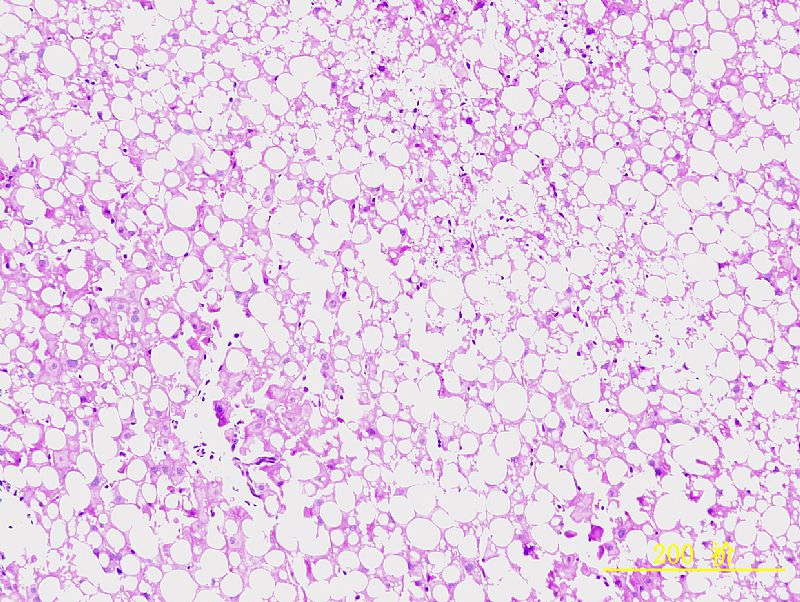

请教各位虫子,我做的是肝纤维模型,皮下注射CCl4 8周造模。每周两次,3ml/kg,40%CCl4。 因为对肝组织的组织形态没有深入的学习,对肝组织的具体病变描述无从入手,不知肝细胞脂肪病变、炎性浸润等是怎样的,附上几张实验图片(HE&Sirus red),请教各位行家,还望各位老师不吝赐教,一一指点下!谢谢大家,另外祝大家节日快乐呵呵 |